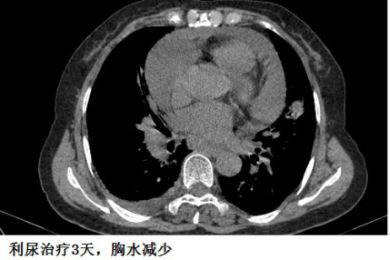

下面的图示,可以帮助大家加深印象!

另外,胸水的病因有时候很难准确判断,最初觉得可能不是心力衰竭引起的,但经验性治疗后,胸水有可能很快减少,这时候贸然按照之前的影像学资料去抽胸水,有可能“干抽”。

这个患者的胸水,应该是心包积液导致静脉回流受阻,体循环淤血引起的。利尿治疗后,胸水减少。